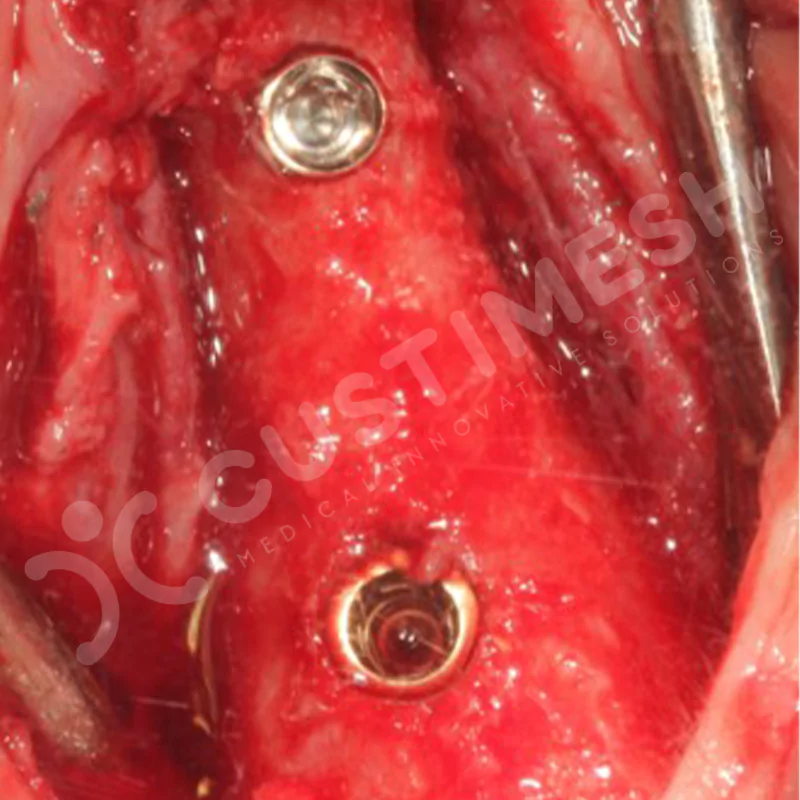

VAKA 1

VAKA 2

VAKA 3